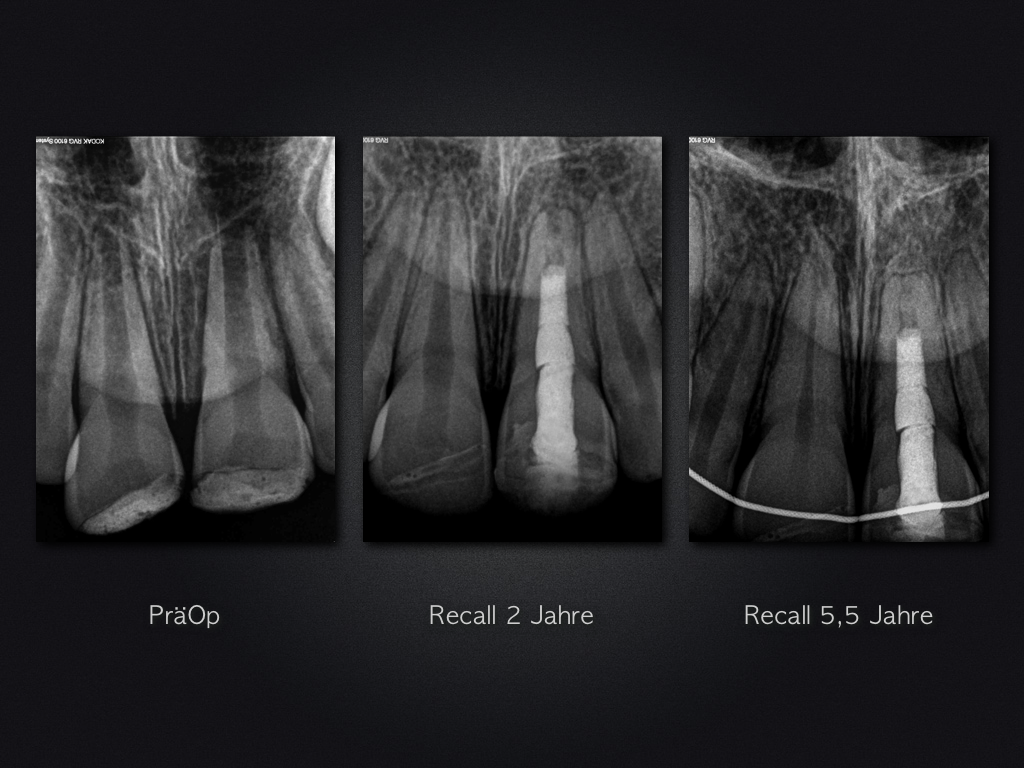

Revitalisierung – Recall nach 5,5 Jahren